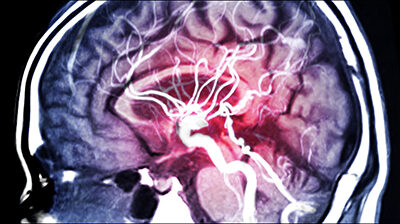

Using equipment funded by VGH & UBC Hospital Foundation donors, researchers found that a cessation of blood flow to the brain and a decrease in the ability of its tissues to uptake oxygen occurred before electrical and mechanical activity in the heart stopped. They also found that brain oxygenation ceased before blood flow throughout the circulatory system.

Sekhon and Bird’s study is the first to use a multimodal approach to monitor brain blood flow and oxygenation during the dying process. Their research involved brain and body blood flow and oxygenation monitoring among 39 patients who underwent the withdrawal of life-sustaining measures, along with 12 healthy controls.

“We also discovered that brain blood flow and brain tissue oxygenation ceased before cardiovascular function in all patients, albeit with slight variations between patients and brain locations,” says Sekhon.